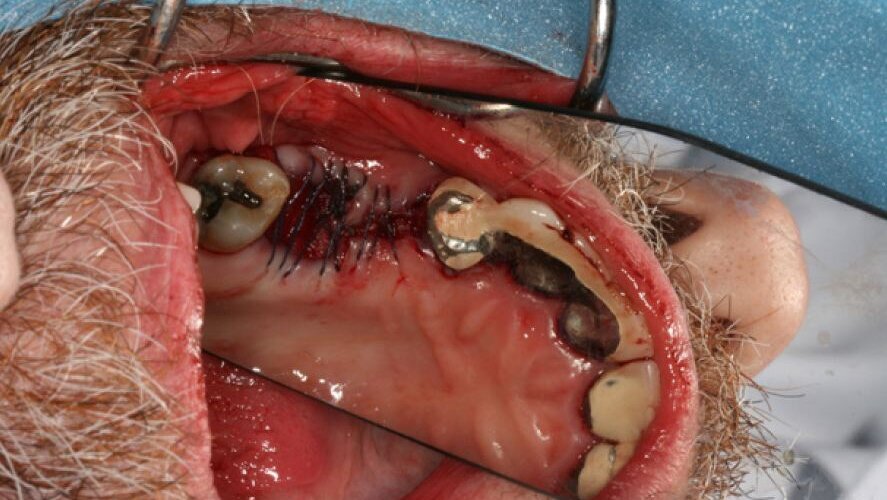

Le processus a impliqué la collecte des cellules souches par une petite incision dans l'os de la hanche du patient, Jason Morgan, le matin de la procédure. À l'aide d'une centrifugeuse, le Dr Ho a isolé et concentré les cellules souches de Morgan, à partir du plasma, et les transplantées dans la mâchoire du patient, puis a ajouté une allogreffe.

Au cours d'un entretien téléphonique avec Dental Tribune, après l'intervention, le Dr Ho a expliqué que les cellules souches travailleront en collaboration avec le tissu environnant pour, à terme, générer des tissu osseux sains, denses dans lesquels l'implant dentaire peut être enfoui en permanence.

Le but ultime de cette procédure, a expliqué le Dr Ho, est de trouver de nouvelles et meilleures méthodes pour la croissance de l'os. "Les cellules souches permettront une croissance osseuse de meilleure qualité et une meilleure guérison, dit-il.

Les cellules souches ont été utilisées pendant de nombreuses années par les neurochirurgiens et les chirurgiens orthopédistes pour générer des os pour des procédures telles que soudure du tibia et des vertèbres. Maintenant, le Dr Ho applique la procédure de greffe de cellules souches pour des applications dentaires et fournir une option pour les patients qui n'ont pas déjà été candidats à un implant dentaire en raison de la faible densité de la mâchoire. Le Dr Ho décrit la procédure ambulatoire comme mini-invasive et relativement indolore et dit qu'il faut entre une et trois heures pour l'effectuer. Il a dit qu'elle devrait fournir une guérison plus rapide, avec moins de douleurs et de meilleurs résultats que d'autres procédures d'implantation.

"Cette procédure peu invasive est une alternative innovante, à long terme à d'autres avancées aux options de remplacement des dents comme les prothèses dentaires, bridges et même aux procédures de greffe osseuse traditionnelles", a expliqué le Dr Ho. "En plus d'offrir une guérison plus rapide et meilleure, la transplantation des propres cellules souches du corps du patient permet d'augmenter la croissance osseuse de la mâchoire par l'angiogenèse pour le soutien en permanence de l'implant dentaire. Parce que l'utilisation de prothèses dentaires et des bridges comportent un risque élevé de problèmes dans de nombreux cas, résultant de la maladie des gencives, de la carie dentaire et de la perte des dents viables, d'autres interventions chirurgicales coûteuses sont nécessaires, là où les implants dentaires sont la solution la plus naturelle pour offrir les meilleurs résultats à long- terme. "